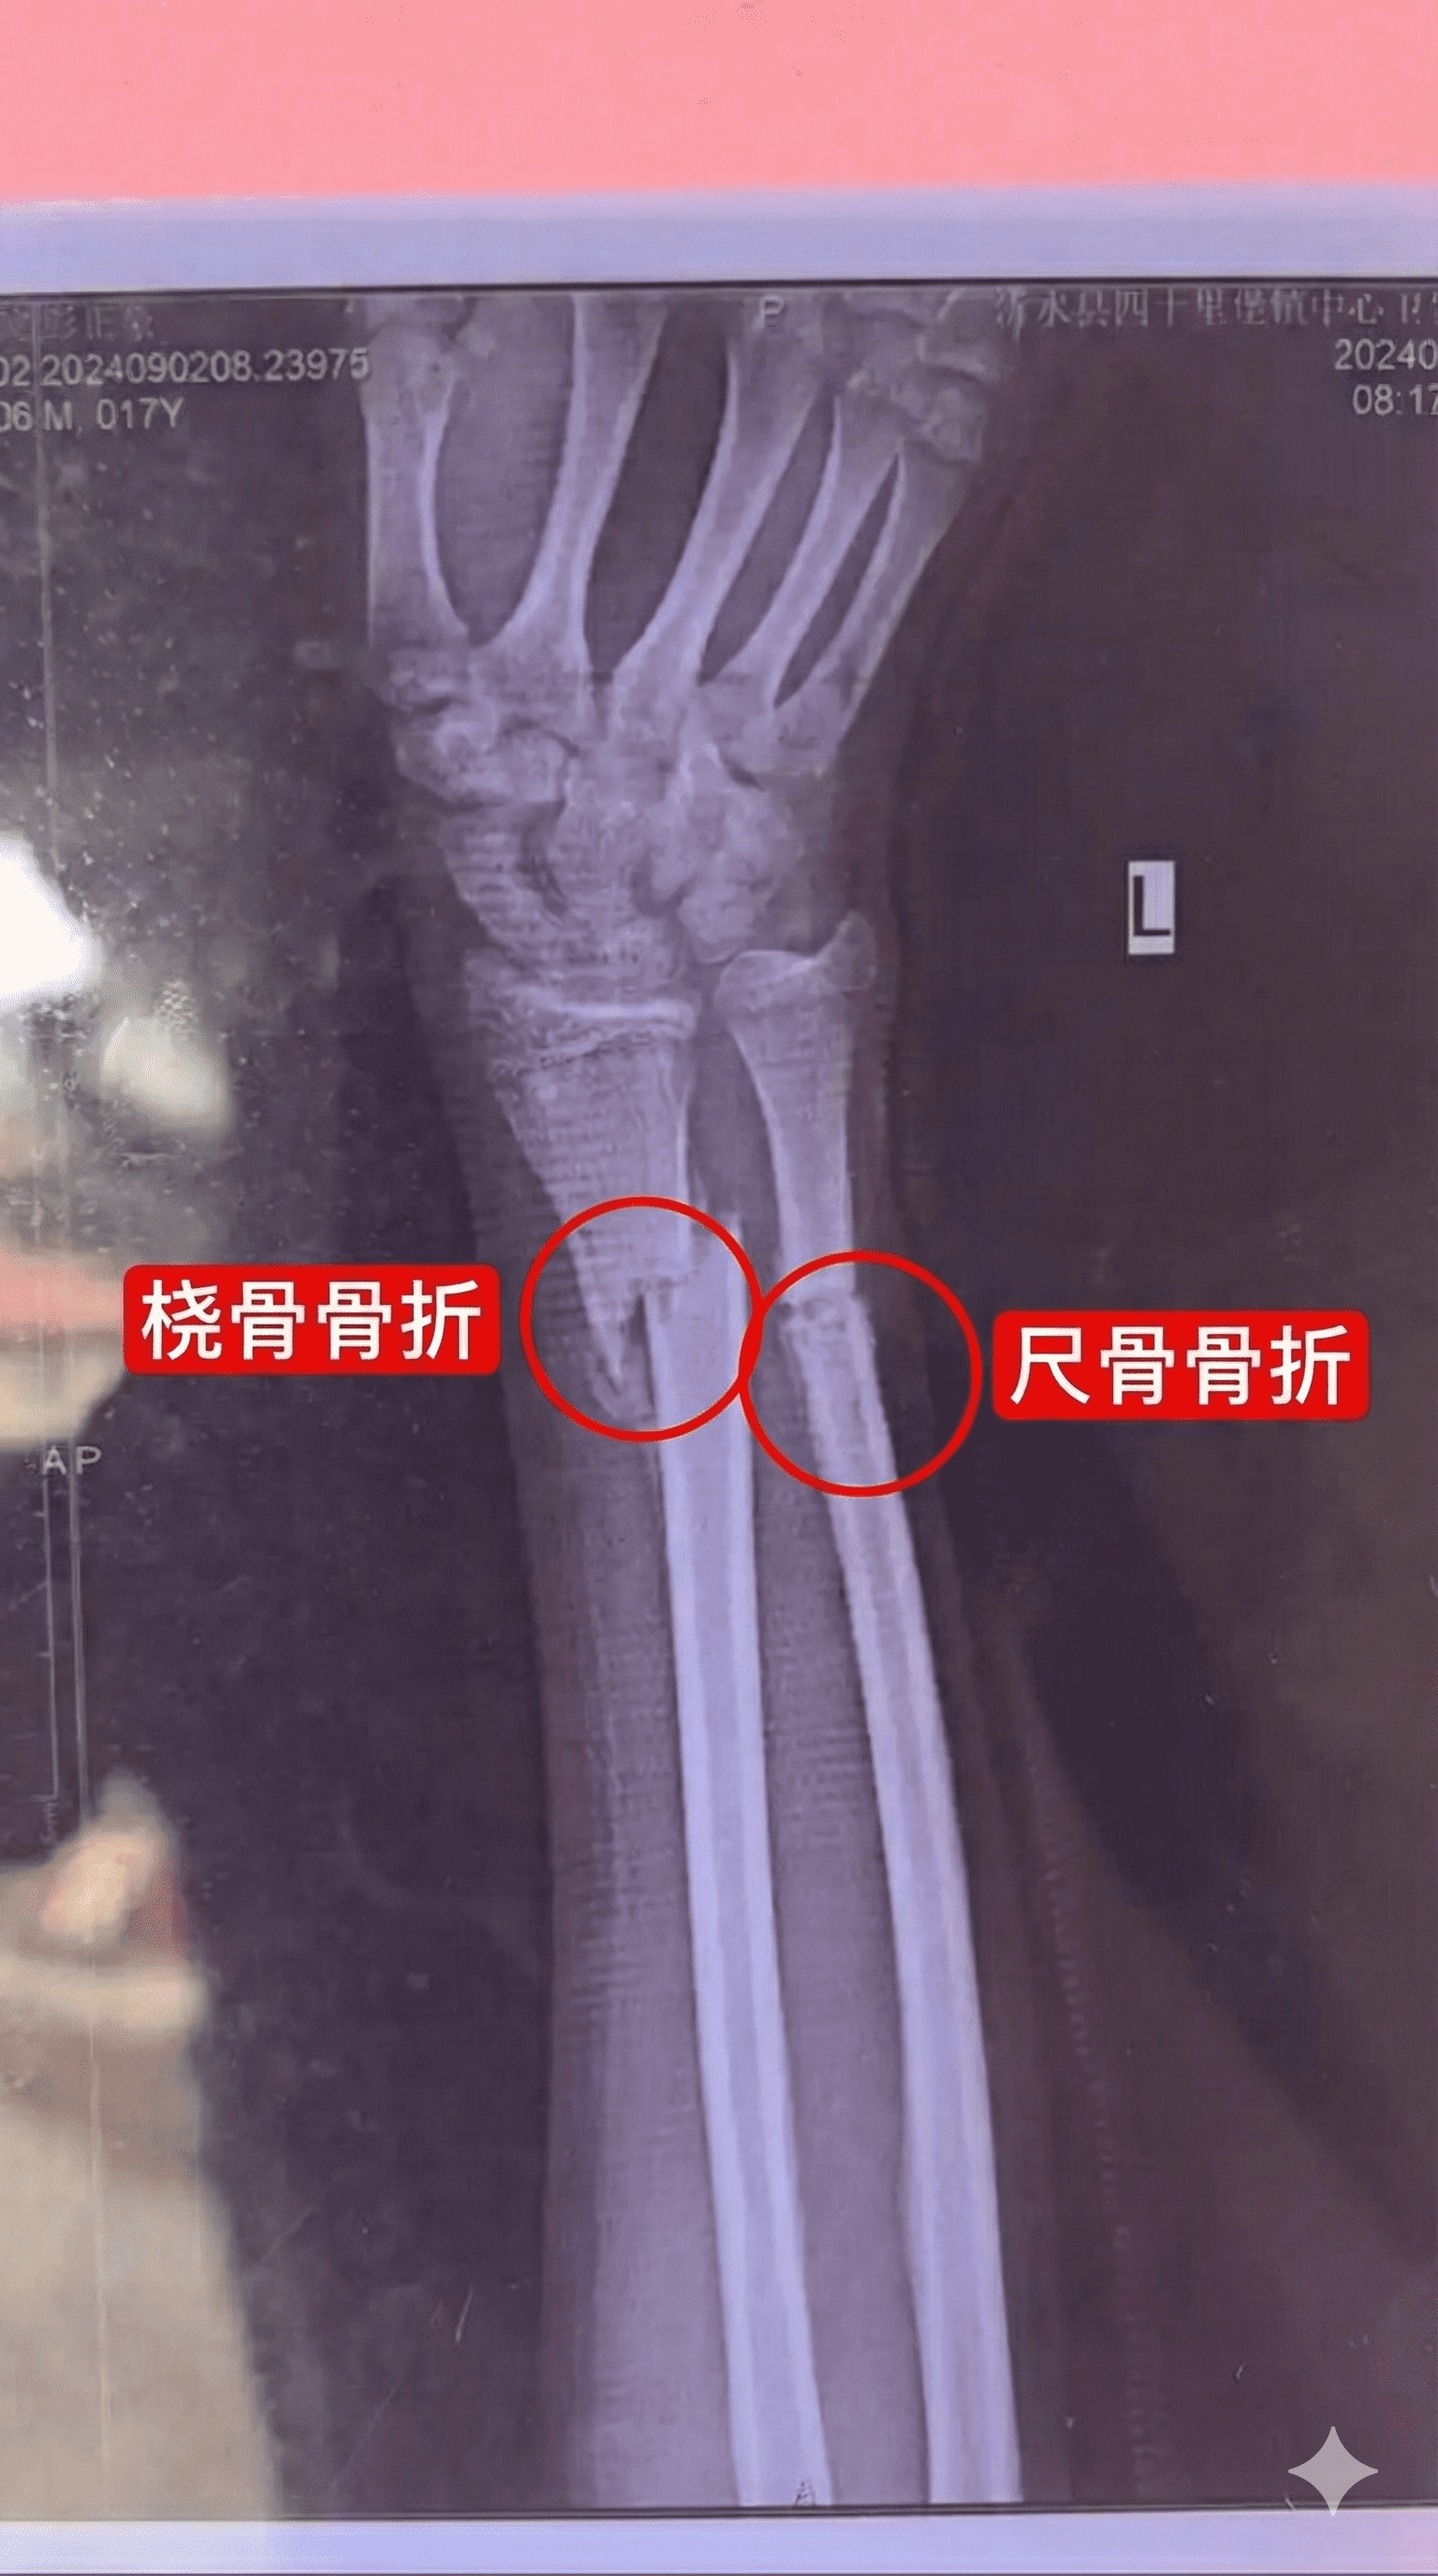

医学影像中文标注